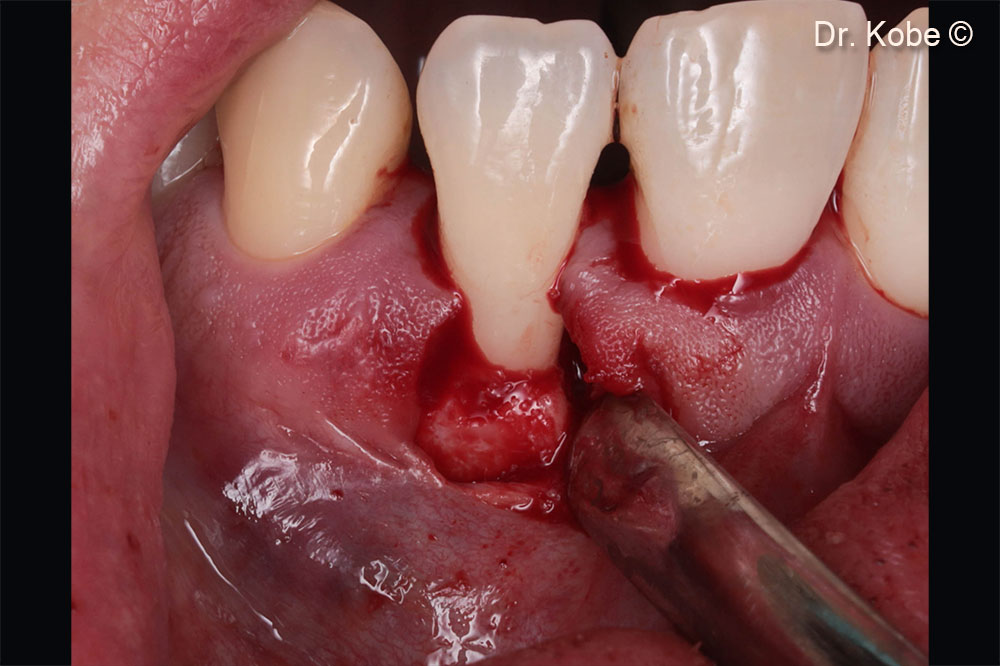

Access to the defect